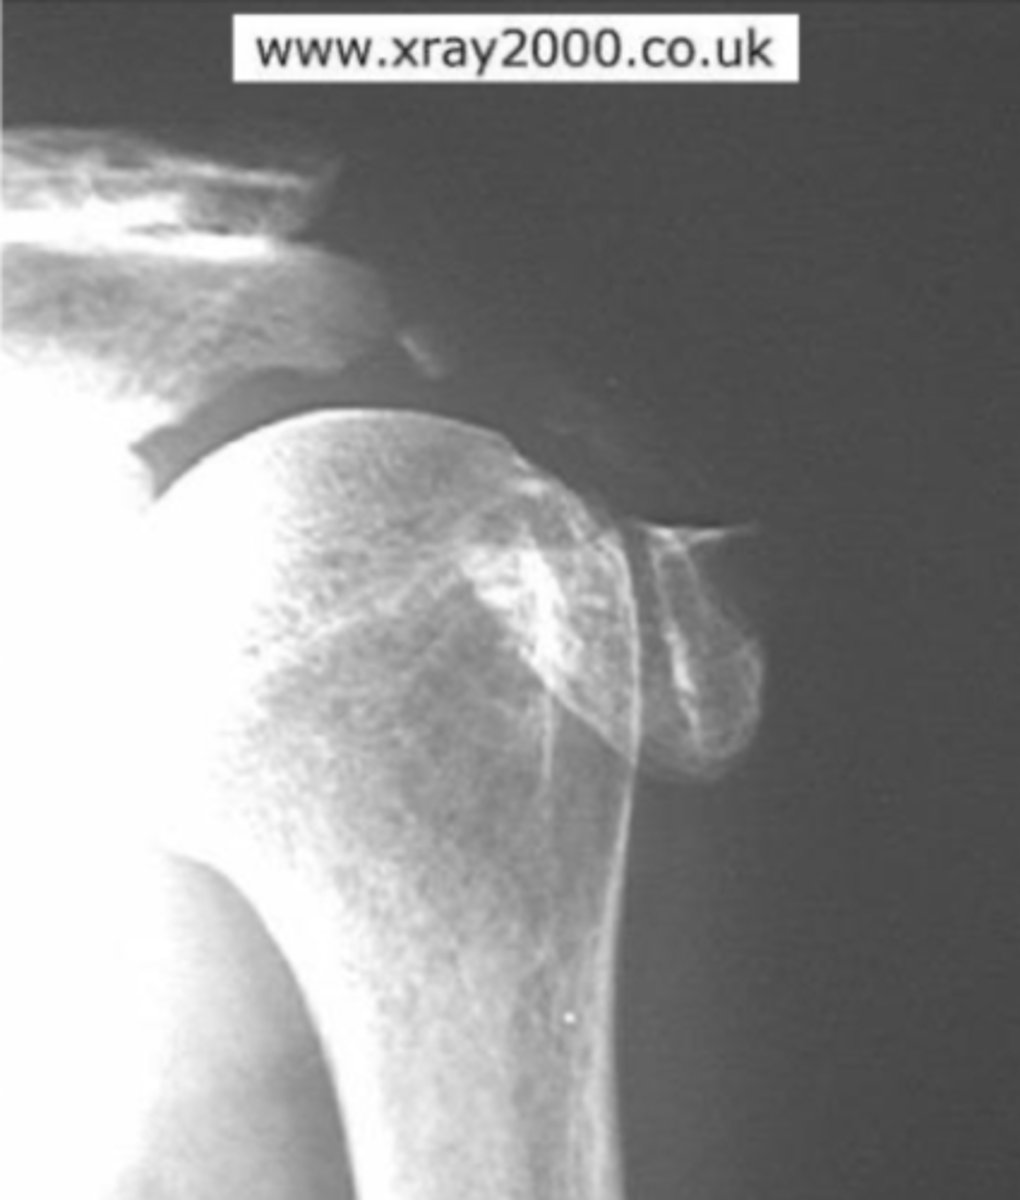

Posterior dislocation of GHJ

What is the issue?